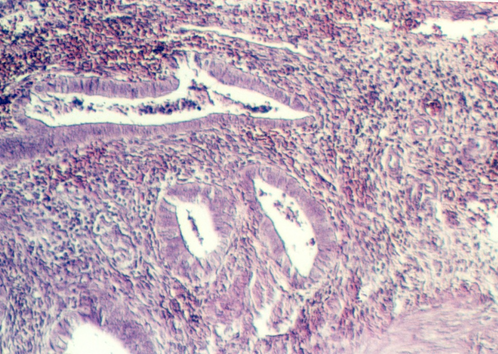

The uterus is a muscular sac, lined with epithelium that undergoes cyclic changes. The wall is made up of thick smooth muscle, organized in interlacing bundles that run randomly. It is called the myometrium In the above photograph, the uterine glands (a part of the endometrium) are seen as straight tubular glands leading to a main lumen. This is diagnostic of the early stage of the cycle or the Proliferative phase. What hormone is secreted by the follicle during this early stage of the cycle?

As stated above, the uterine lining consists of glands that are called "endometrium" As the ovary and oviduct are undergoing changes with the cycle, the uterine lining is being prepared to receive an embryo. The normal human menstral cycle is divided into three phases by the hormonal events and changes in the uterine lining. The first phase is called the Proliferative phase. This coincides with the rise in estrogens early in the cycle and is distinguished in the uterus by lengthening endometrial glands.

Slide 86 shows a uterus in the proliferative phase. The endometrium is illustrated in the photograph below. Note that the cells are low columnar to high columnar. The glands are relatively straight with a narrow lumina. Outside the glands is the highly cellular lamina propria. The following photos illustrate the proliferative phase with higher magnifications.